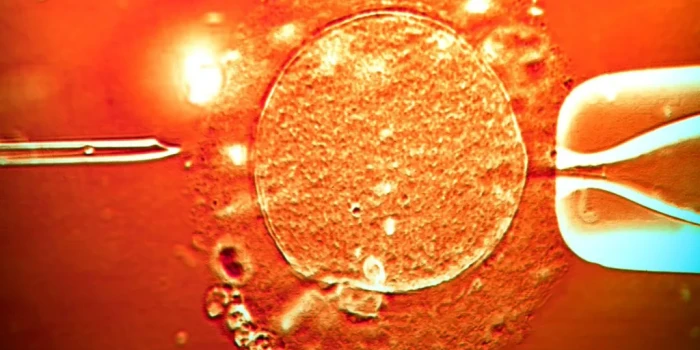

Սարսափելի ժառանգություն. Քաղցկեղ առաջացնող գենով դոնորի սերմնահեղուկով Եվրոպայում ծնվել է գրեթե 200 երեխա Հետաքննությունը, որին մասնակցել է 14 հանրային հեռուստաընկերություն՝ ներառյալ BBC-ն, բացահայտել է, որ մի անանուն դոնորի սերմնահեղուկով, որն առանց ինքն էլ իմանալու կրում էր ծանր գենետիկական մուտացիա, Եվրոպայում ծնվել է առնվազն 197 երեխա: Մուտացիան վնասում է TP53 գենը և հանգեցնում Լի-Ֆրաումենի համախտանիշի, որի դեպքում մարդու ողջ կյանքի ընթացքում քաղցկեղ զարգացնելու հավանականությունը հասնում է 90%-ի, հաճախ՝ մանկությունից: Մի քանի երեխա արդեն մահացել է, շատերը տառապում են քաղցկեղի մի քանի տեսակներից: Դոնորը առողջ է, նա սերմնահեղուկ է հանձնել 2005 թվականից՝ որպես ուսանող, և անցել է բոլոր ստուգումները: Սակայն նրա սերմնաբջիջների մինչև 20%-ը պարունակում է վտանգավոր մուտացիա, որը փոխանցվում է երեխային ամեն բջիջում: Սերմնահեղուկը վաճառել է Դանիայի European Sperm Bank-ը: Այն չի մատակարարվել բրիտանական կլինիկաներ, սակայն մի քանի բրիտանական ընտանիքներ, որոնք բուժում են անցել Դանիայում, օգտվել են այդ դոնորից և արդեն տեղեկացվել են: Բանկը հայտարարել է, որ «անմիջապես արգելափակել» է դոնորին, երբ խնդիրը բացահայտվել է, և խոստովանել, որ որոշ երկրներում թույլատրելի քանակից շատ ավելի երեխաներ են ծնվել: Օրինակ՝ Բելգիայում, որտեղ թույլատրվում է ընդամենը 6 ընտանիք մեկ դոնորի համար, այդ սերմնահեղուկով ծնվել է 53 երեխա 38 կնոջից: Ֆրանսիացի միայնակ մայր Սելինը (անունը փոխված է), ում դուստրը ծնվել է այդ դոնորի սերմնահեղուկով 14 տարի առաջ, պատմում է. «Ես բացարձակապես չեմ մեղադրում դոնոր

ին, բայց անընդունելի է, որ ինձ տրվեց «ոչ մաքուր», վտանգ պարունակող սերմնահեղուկ: Հիմա քաղցկեղը մեզ հետ կլինի ամբողջ կյանքում: Չգիտենք՝ երբ, որ տեսակի և քանի անգամ»: Աշխարհում օրենք չկա, թե քանի երեխա կարելի է ունենալ մեկ դոնորից: Յուրաքանչյուր երկիր ինքն է սահմանում սահմանափակումներ, բայց մեծ միջազգային բանկերը հաճախ խախտում են դրանք: Մանչեսթերի համալսարանի պրոֆեսոր Ալան Փեյսին նշում է՝ Մեծ Բրիտանիայի սերմնահեղուկի կեսն արդեն ներմուծվում է, և հենց այստեղ է ծագում խնդիրը: Մասնագետները համակարծիք են՝ նման դեպքերը չափազանց հազվադեպ են, և լիցենզավորված կլինիկաներում սերմնահեղուկն ավելի մանրակրկիտ է ստուգվում, քան շատ հայրերից բնական ճանապարհով ծնված երեխաների դեպքում: Սակայն այս գործը կրկին բարձրացրել է հարցը՝ անհրաժեշտ է արդյոք խիստ միջազգային սահմանափակումներ և ավելի լայն գենետիկ սկրինինգ: